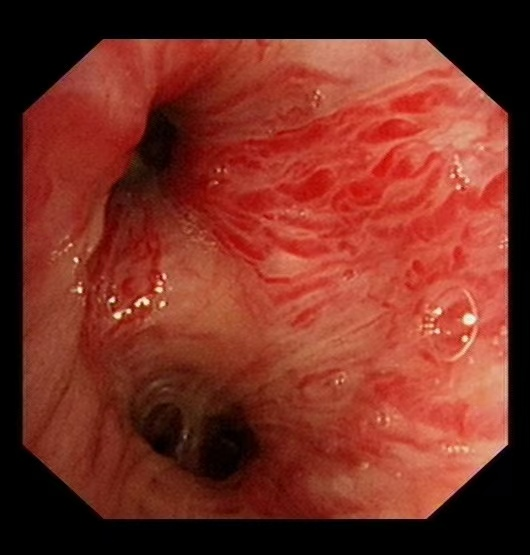

58岁的汪先生(化名)因大咯血入院,虽生命体征平稳,但出血症状持续未缓解。经支气管镜检查发现,其左侧支气管内存在浸润性新生物,表面血管扭曲、血供丰富,随时可能再次出现大咯血,病情十分凶险。

“支气管淀粉样变发病率极低,极易误诊漏诊!”我院呼吸与危重症医学科副主任(主持工作)王开金副主任医师介绍,该病由淀粉样物质异常沉积于气道引发,临床表现缺乏特异性,确诊必须依赖病理活检。“此例患者出血风险极高,活检操作犹如‘刀尖起舞’。”王开金表示,团队通过血管介入止血、支气管镜精准定位和快速病理检测,实现了“诊断-治疗”一体化,为患者抢得生机。